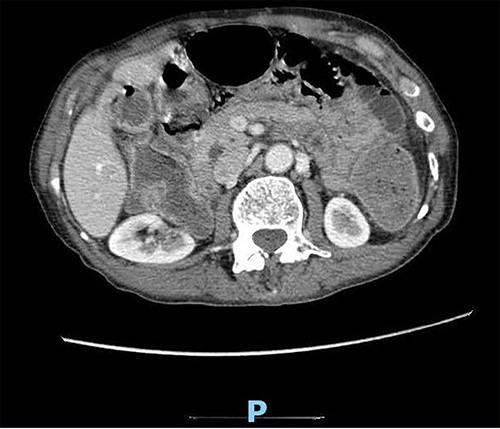

Upon clinical examination, the patient was vitally stable. Abdominal examination revealed a distended abdomen with generalized tenderness. Digital rectal examination revealed an empty rectum with no palpable masses. Laboratory investigations were unremarkable (Table 1). Abdominal X-ray was done (Fig. 2) and showed dilated large bowel loops suggestive of bowel obstruction. Enhanced CT scan of the abdomen and pelvis was obtained (Figs 3–5) and showed a dilated large bowel loop, with air fluid level. A 2.5-cm gallstone was noted, impacting the sigmoid colon and causing partial large bowel obstruction. There was evidence of pneumobilia with air foci within the gallbladder with a suspected fistula with the hepatic flexure.

Enhanced CT scan of the abdomen showing a gallbladder stone impacted at the sigmoid colon, with a significantly enlarged prostate causing narrowing of the rectosigmoid junction (axial view).